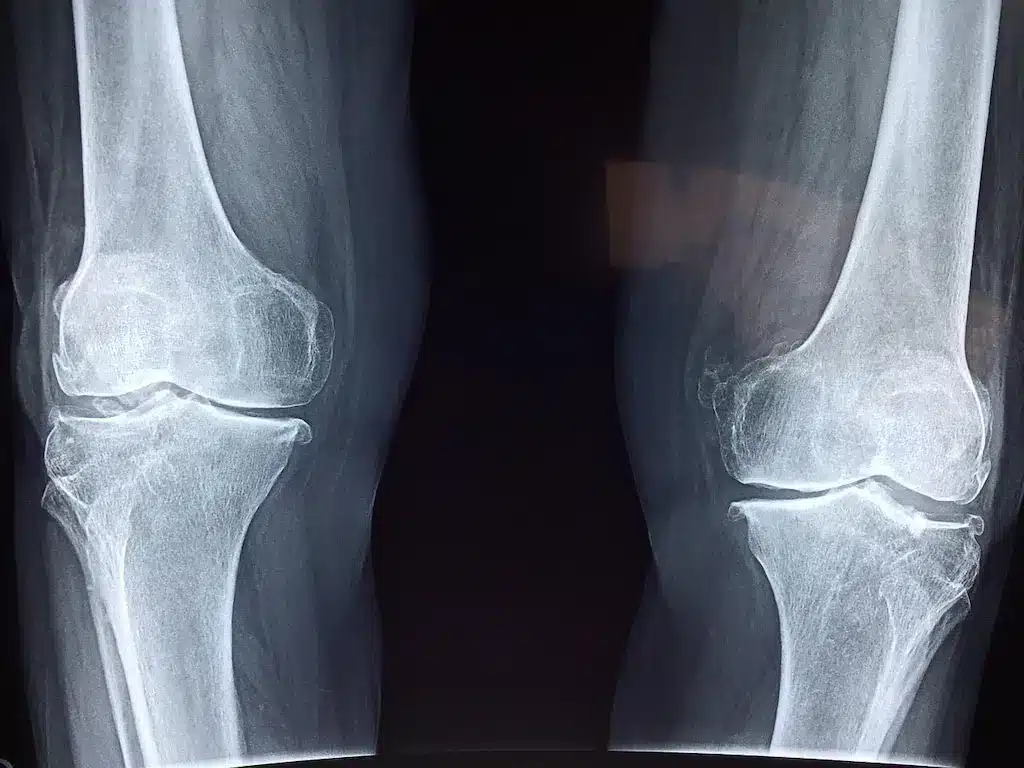

Osteoartrite de joelho: o que é, sintomas, diagnóstico e tratamentos

No começo, a osteoartrite de joelho nem sempre chama tanta atenção. A dor pode surgir em alguns movimentos, o joelho…